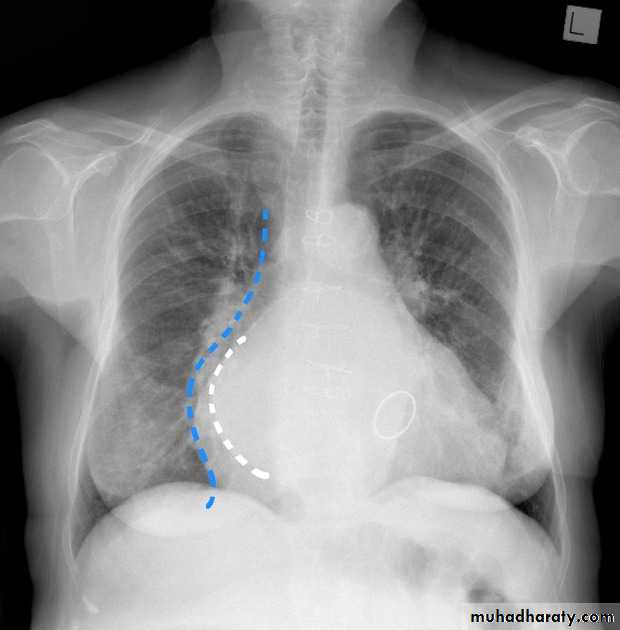

Mitral valve disease

Mitral valve disease (double density RT cardiac border)

15.mitral valve disease & their sign

16.MVD